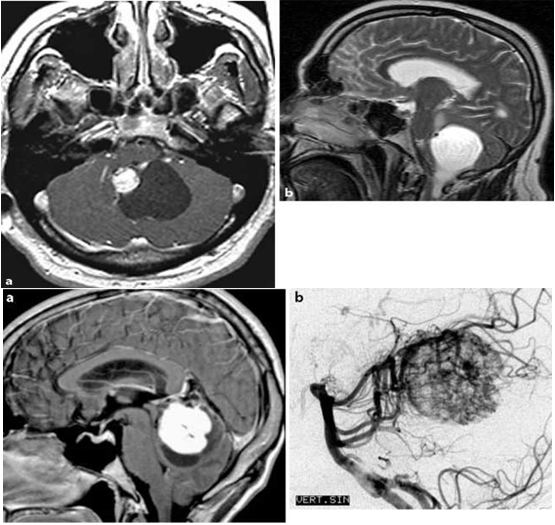

Hình 3: Các loại khác nhau của HB trên MRI sọ não (xung T1).

(A): U nang liên kết của Hemangiomblastoma vùng cầu não

(B): U đặc Hemangiomblastoma vùng tiểu não